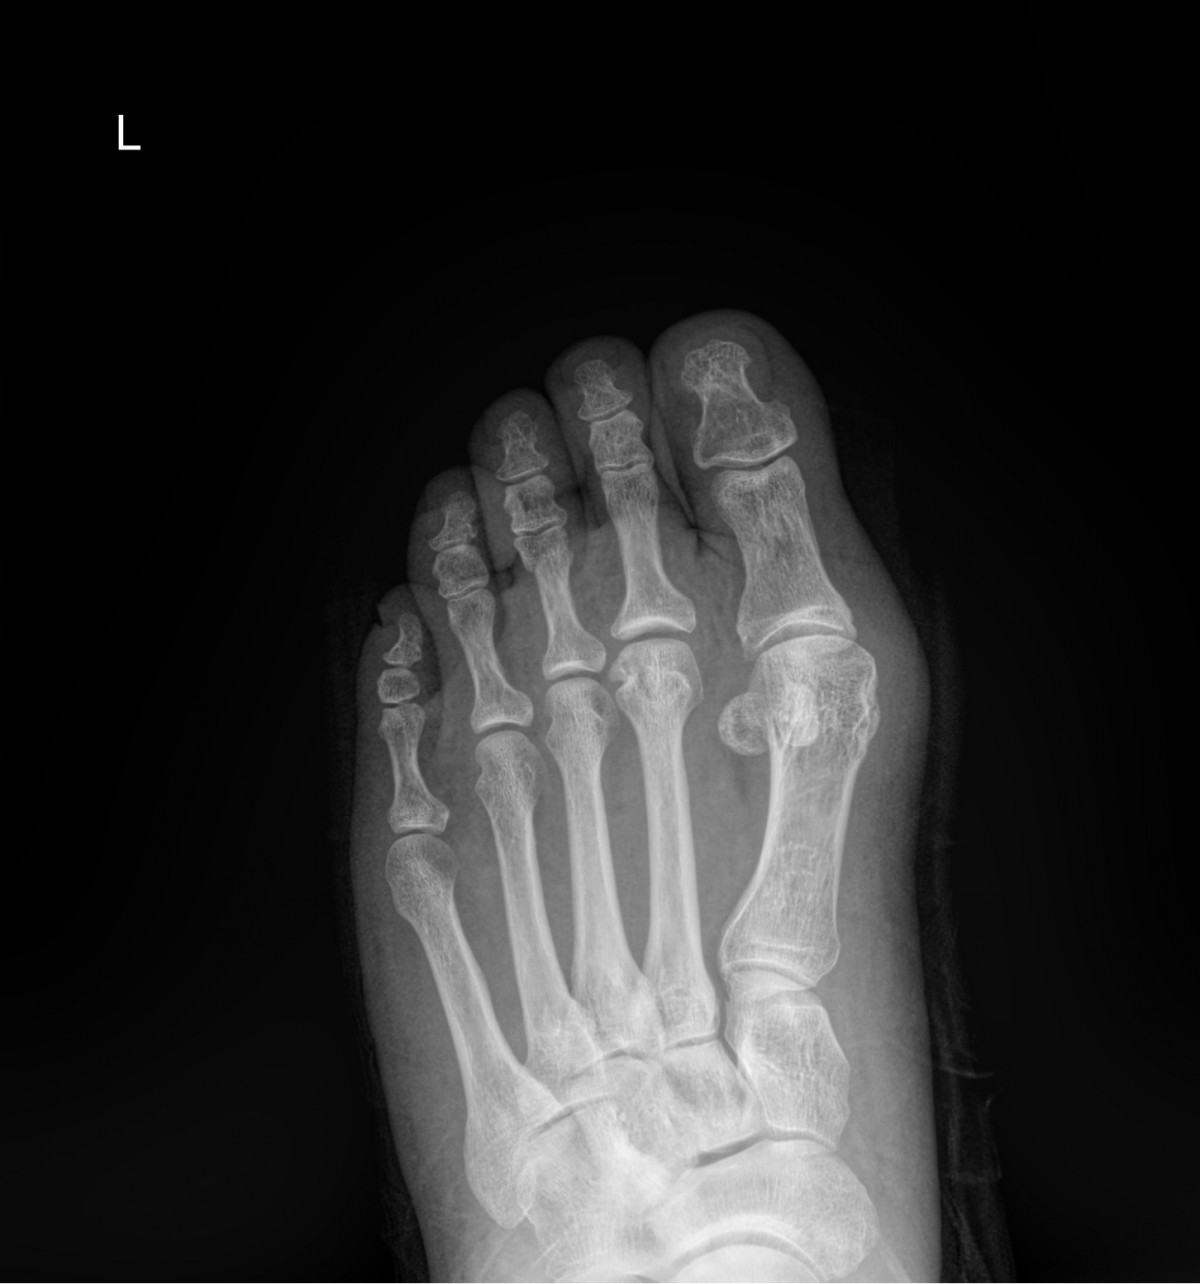

정지영원장님 발가락 골절 수술 이금O 환자

dae765e4d9ac96aee867c9d6292d8784_1758008584_406.jpg